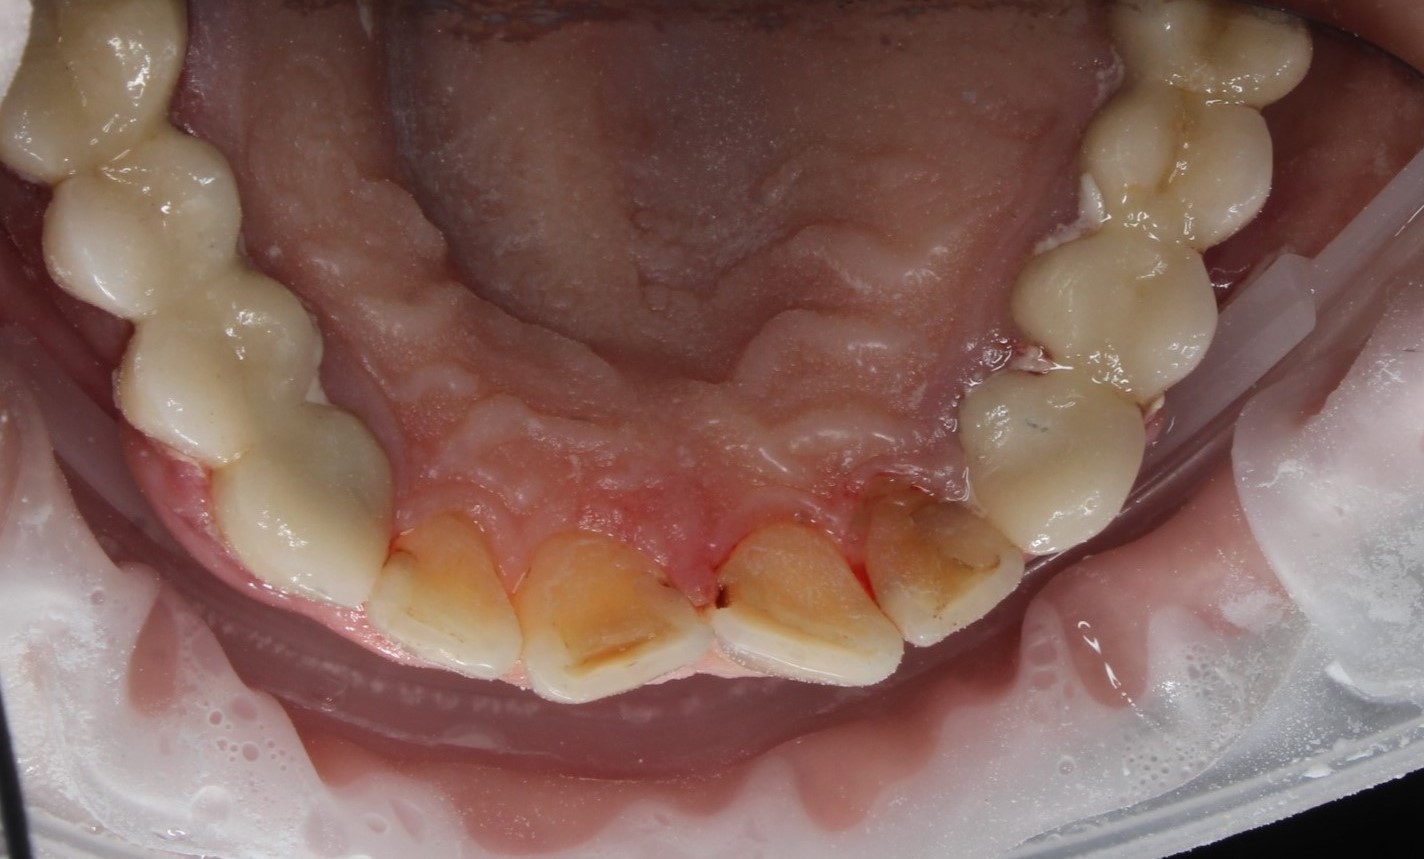

Профессиональная гигиена нижней фронтальной группы зубов

Во время процедуры был удален пигментированный зубной налет и камень, а также проведена полировка зубов.